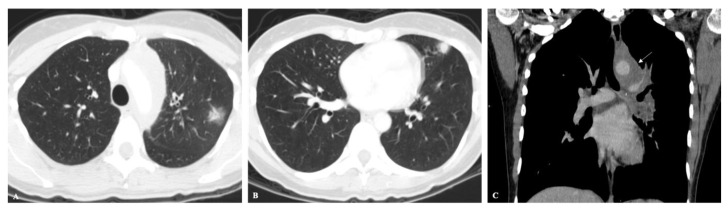

Endemic fungal infections are responsible for high rates of morbidity and mortality in certain regions of the world. The diagnosis and management remain a challenge, and the reason could be explained by the lack of disease awareness, variability of symptoms, and insidious and often overlooked clinical presentation. Imaging findings are nonspecific and frequently misinterpreted as other more common infectious or malignant diseases. Patient demographics and clinical and travel history are important clues that may lead to a proper diagnosis. The purpose of this paper is to review the presentation and differential diagnosis of endemic mycoses based on the most common chest imaging findings.